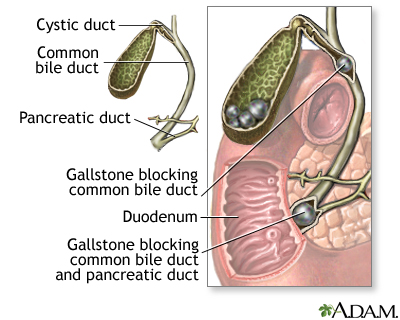

Choledocholithiasis means there is at least one gallstone in the common bile duct. The stone may be made up of bile pigments or calcium and cholesterol salts and are called common bile duct stones.

About 1 in 7 people with gallstones will develop stones in the common bile duct. This is the small tube that carries bile from the gallbladder to the intestine.

The goal of treatment is to relieve the blockage of the common bile duct.

- ERCP and a procedure called a sphincterotomy, which makes a surgical cut into the muscle in the common bile duct to allow stones to pass or be removed

- Pancreatitis